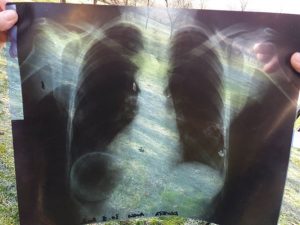

– Znao sam da moram da učinim sve da je spasem. Nekako sam je smjestio u kola, i od šoka se i ne sjećam kako sam je dovezao do prijedorske Hitne pomoći. Tamo su nam rekli da hitno moramo u bolnicu, gdje je snimak pokazao da je metak udaljen svega pola centimetra od srčane aorte – prisjeća se Drago.

Zbog ozbiljnosti povreda Anka je hitno transportovana u UKC u Banjaluci, gdje je i operisana. Čudom je preživjela i uspješno se oporavila! Utvrđeno je da je riječ o metku ispaljenom iz puške kalibra M48, ali ni do danas nije utvrđeno ko je pucao i odakle.